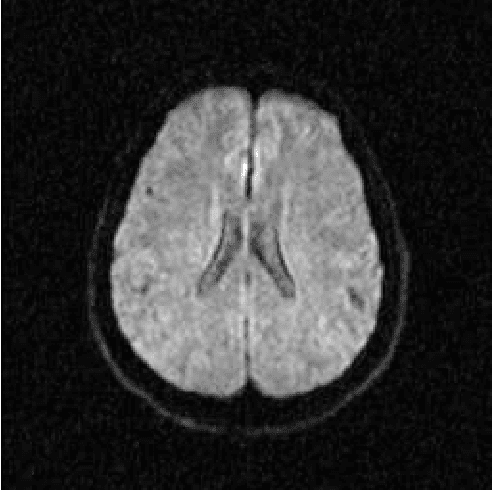

Abstract:Alzheimer's disease is the most common cause of dementia, yet difficult to accurately diagnose without the use of invasive techniques, particularly at the beginning of the disease. This work addresses the classification and analysis of multispectral synthetic images composed by diffusion-weighted magnetic resonance brain volumes for evaluation of the area of cerebrospinal fluid and its correlation with the progression of Alzheimer's disease. A 1.5 T MR imaging system was used to acquire all the images presented. The classification methods are based on multilayer perceptrons and classifiers of radial basis function networks. It is assumed that the classes of interest can be separated by hyperquadrics. A polynomial network of degree 2 is used to classify the original volumes, generating a ground-truth volume. The classification results are used to improve the usual analysis by the map of apparent diffusion coefficients.

Abstract:Multispectral image analysis is a relatively promising field of research with applications in several areas, such as medical imaging and satellite monitoring. A considerable number of current methods of analysis are based on parametric statistics. Alternatively, some methods in Computational Intelligence are inspired by biology and other sciences. Here we claim that Philosophy can be also considered as a source of inspiration. This work proposes the Objective Dialectical Method (ODM): a method for classification based on the Philosophy of Praxis. ODM is instrumental in assembling evolvable mathematical tools to analyze multispectral images. In the case study described in this paper, multispectral images are composed of diffusion-weighted (DW) magnetic resonance (MR) images. The results are compared to ground-truth images produced by polynomial networks using a morphological similarity index. The classification results are used to improve the usual analysis of the apparent diffusion coefficient map. Such results proved that gray and white matter can be distinguished in DW-MR multispectral analysis and, consequently, DW-MR images can also be used to furnish anatomical information.

Abstract:The unsupervised classification has a very important role in the analysis of multispectral images, given its ability to assist the extraction of a priori knowledge of images. Algorithms like k-means and fuzzy c-means has long been used in this task. Computational Intelligence has proven to be an important field to assist in building classifiers optimized according to the quality of the grouping of classes and the evaluation of the quality of vector quantization. Several studies have shown that Philosophy, especially the Dialectical Method, has served as an important inspiration for the construction of new computational methods. This paper presents an evaluation of four methods based on the Dialectics: the Objective Dialectical Classifier and the Dialectical Optimization Method adapted to build a version of k-means with optimal quality indices; each of them is presented in two versions: a canonical version and another version obtained by applying the Principle of Maximum Entropy. These methods were compared to k-means, fuzzy c-means and Kohonen's self-organizing maps. The results showed that the methods based on Dialectics are robust to noise, and quantization can achieve results as good as those obtained with the Kohonen map, considered an optimal quantizer.

Abstract:The materialist dialectical method is a philosophical investigative method to analyze aspects of reality. These aspects are viewed as complex processes composed by basic units named poles, which interact with each other. Dialectics has experienced considerable progress in the 19th century, with Hegel's dialectics and, in the 20th century, with the works of Marx, Engels, and Gramsci, in Philosophy and Economics. The movement of poles through their contradictions is viewed as a dynamic process with intertwined phases of evolution and revolutionary crisis. In order to build a computational process based on dialectics, the interaction between poles can be modeled using fuzzy membership functions. Based on this assumption, we introduce the Objective Dialectical Classifier (ODC), a non-supervised map for classification based on materialist dialectics and designed as an extension of fuzzy c-means classifier. As a case study, we used ODC to classify 181 magnetic resonance synthetic multispectral images composed by proton density, $T_1$- and $T_2$-weighted synthetic brain images. Comparing ODC to k-means, fuzzy c-means, and Kohonen's self-organized maps, concerning with image fidelity indexes as estimatives of quantization distortion, we proved that ODC can reach almost the same quantization performance as optimal non-supervised classifiers like Kohonen's self-organized maps.

Abstract:Alzheimer's disease is the most common cause of dementia, yet hard to diagnose precisely without invasive techniques, particularly at the onset of the disease. This work approaches image analysis and classification of synthetic multispectral images composed by diffusion-weighted magnetic resonance (MR) cerebral images for the evaluation of cerebrospinal fluid area and measuring the advance of Alzheimer's disease. A clinical 1.5 T MR imaging system was used to acquire all images presented. The classification methods are based on multilayer perceptrons and Kohonen Self-Organized Map classifiers. We assume the classes of interest can be separated by hyperquadrics. Therefore, a 2-degree polynomial network is used to classify the original image, generating the ground truth image. The classification results are used to improve the usual analysis of the apparent diffusion coefficient map.